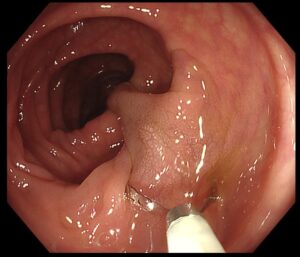

S状結腸に約25mmの有茎性ポリープ(Ip型) を発見しました🍄(写真1)

(写真1)